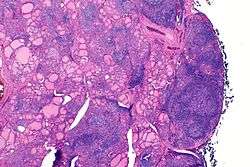

The thyroid of someone with Hashimoto's thyroiditis as seen with a microscope at low magnification

Histologically, the hypersensitivity is seen as diffuse parenchymal infiltration by lymphocytes, particularly plasma B-cells, which can often be seen as secondary lymphoid follicles (germinal centers, not to be confused with the normally present colloid-filled follicles that constitute the thyroid). Atrophy of the colloid bodies is lined by Hürthle cells, cells with intensely eosinophilic, granular cytoplasm, a metaplasia from the normal cuboidal cells that constitute the lining of the thyroid follicles. Severe thyroid atrophy presents often with denser fibrotic bands of collagen that remains within the confines of the thyroid capsule.[17]